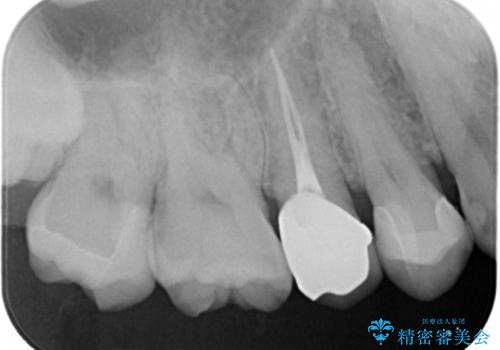

視診では明らかに食べ物が詰まっているのがわかり、レントゲン写真では大きな虫歯の像が確認されました。

虫歯の大きさ次第でクラウンかインレーのどちらかになるだろうとご説明させていただき、今回はセラミックインレーでの治療となりました。

- 右上7 セラミックインレー 77000円×1本費用は治療当時の料金となります